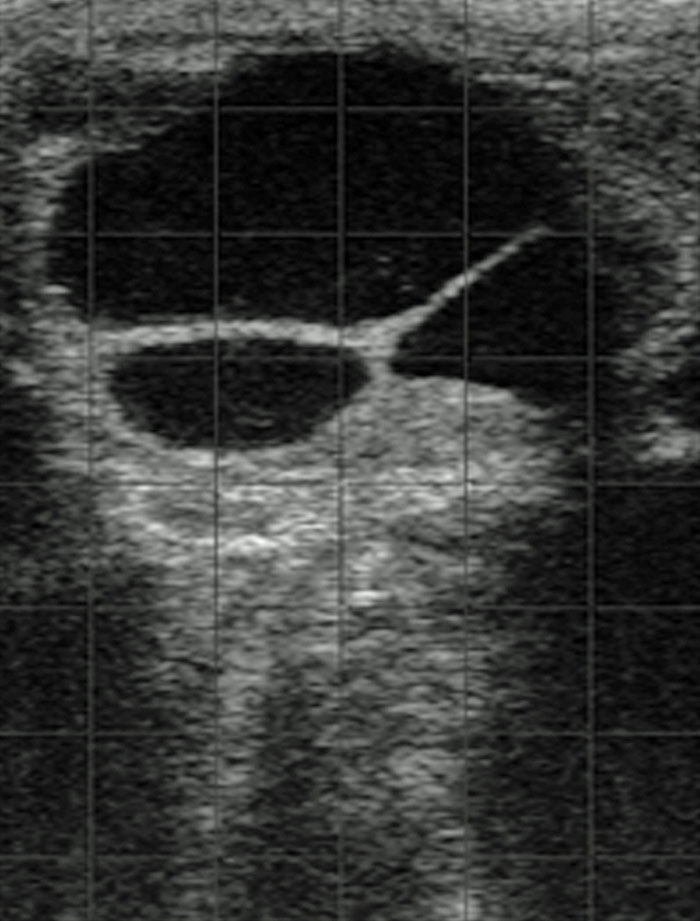

Ovarian cysts can be identified by transrectal ultrasonography as follicles typically larger than normal ovulatory follicles, with an increased overall ovarian diameter along with a flaccid uterus in the absence of a corpus luteum, while cows in pro-oestrus have an erect turgid uterus. Differentiating from true anoestrus is not difficult because these cows have small ovaries with minimum follicular development.

Ultrasonography assists in distinguishing between follicular and luteinised cysts, and reliable identification of a corpus luteum. A luteal cyst is characterised by enlarged ovaries with one or more cysts with thicker walls (greater than 3mm) than those of thin-walled follicular cysts. Luteal cysts are associated with high concentrations of progesterone (due to their luteal tissue lining), while follicular cysts are associated with relatively low concentrations of progesterone (Jeffcoate and Ayliffe, 1995). Progesterone concentration measurement may also help determine the degree of luteinisation of an ovarian cyst.